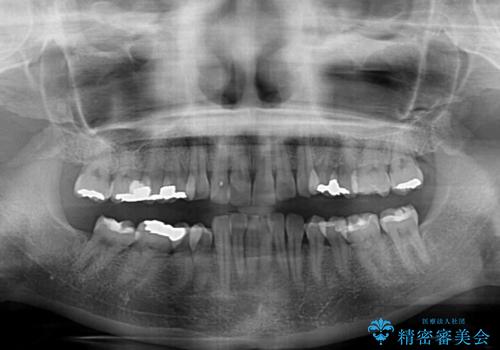

- 前歯のディープバイトと叢生を気にして来院された患者様です。

目立ちにくい装置を希望されていたため、ワイヤー装置とインビザラインを提案したところ、インビザラインを希望されました。

下顎大臼歯が手前に倒れていたため、起き上がらせることで咬み合わせ高さを挙上し、ディープバイトと叢生を改善することとしました。